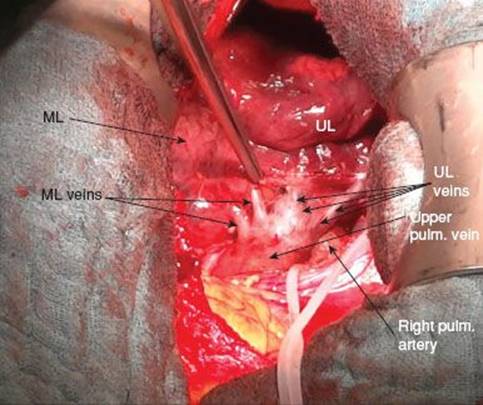

Dissection of Veins

Dissection is started at the upper pulmonary vein with exposure of the branches to the middle lobe and those to the upper lobe. A small sponge stick is used for blunt dissection of surrounding tissue from the vessel wall. Mobilization of the different veins is facilitated by pushing toward the lung parenchyma. The branching of the pulmonary vein becomes visible, allowing identification of the parts to the middle and upper lobe (Fig. 11.4). Once the middle lobe veins are clearly identified, a right-angle clamp is passed behind the vessel and a suture or small vessel loop (1 mm) may be placed to lift the vein up for better dissection of its posterior wall. Directly behind the vein, the interlobar artery is located. Care has to be taken to stay away from the underlying interlobar pulmonary artery which sometimes sends early branches to the middle lobe that may be harmed if the clamp is passed too forcefully. The wall of the artery usually presents as a more yellow structure behind the vein which appears more bluish because of its thinner vessel wall.

Figure 11.3 Mediastinal pleura incised exposing partially dissected upper pulmonary vein and arteries to middle and lower lobe as well as lymph nodes.

Figure 11.4 Exposure of venous branches to middle and upper lobe.